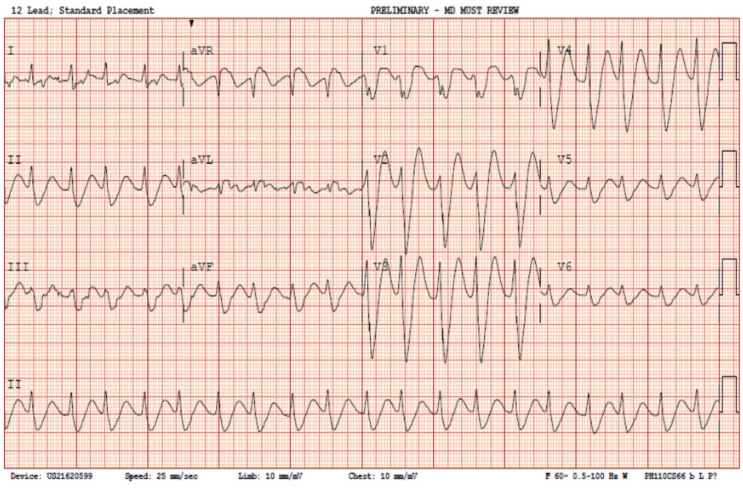

Further rhythm review on serial ECGs showed varying frontal axes with a broad QRS (Figure 2). Device interrogation demonstrated an AS-VS rhythm consistent with a supraventricular tachycardia (SVT) with aberrancy as the culprit arrhythmia (Figure 3) corresponding to the approximate time of the initial ECG. On further review of the interrogation, several episodes of nonsustained VT as well as a prolonged episode of VT were observed earlier in the day (Figure 4). This prolonged episode of VT was thought to be temporally consistent with the presenting syncopal episode. Flecainide toxicity was suspected, and a drawn level was elevated at 1.06 mcg/mL (normal <1.0 mcg/ml). Given high suspicion for flecainide toxicity, the amiodarone infusion was thus discontinued. Medical toxicology was consulted and a NaHCO₃ drip was initiated with a target alkaline pH of 7.45-7.55.